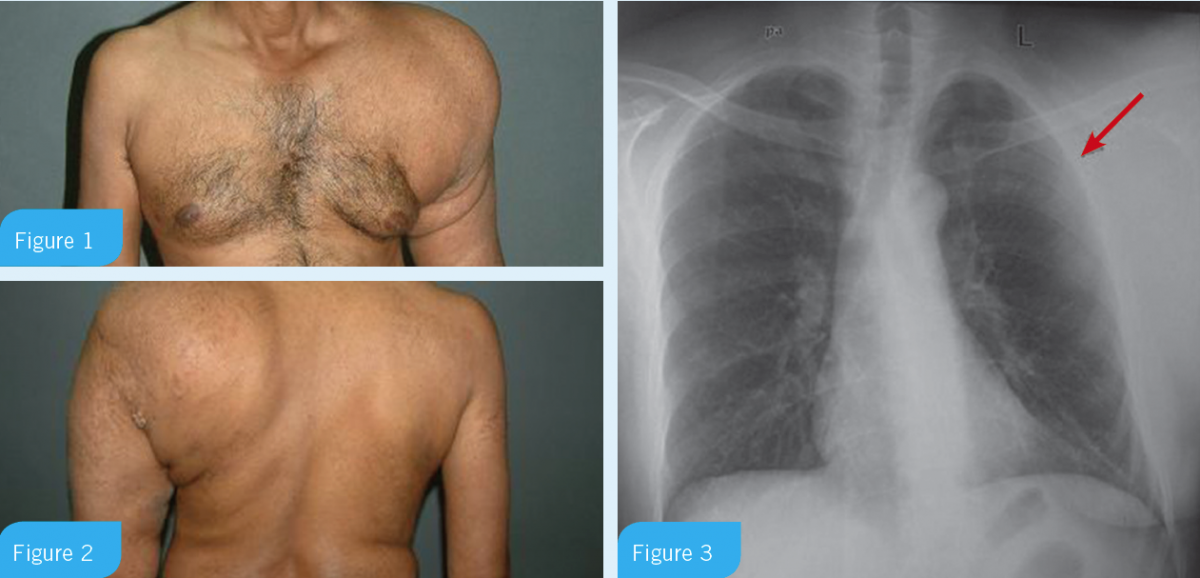

A middle-aged man came to the ambulatory clinic with left side chest discomfort and painless increase in girth of his left shoulder for last decade (Figure 1 and 2). He reported no similar swelling of the other limbs nor was he living in area endemic to filariasis.

Physical exam revealed asymmetric diffuse enlargement of the left shoulder and arm with normal neck and supraclavicular soft tissue.

Blood tests were unremarkable. Chest radiograph showed decreased left lung volume with compression (Figure 3).

A middle-aged man came to the ambulatory clinic with left side chest discomfort and painless increase in girth of his left shoulder for last decade (Figures 1 and 2). He reported no similar swelling of the other limbs nor was he living in area endemic to filariasis. He had no similar family history and he was lifetime non-alcoholic. Physical exam revealed asymmetric diffuse enlargement of the left shoulder and arm with normal neck and supraclavicular soft tissue. Blood tests were unremarkable. Chest radiograph showed decreased left lung volume with compression (Figure 3).